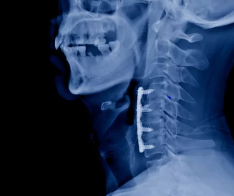

1. 경추 전방 고정술 (ACDF): 목 앞쪽에 작은 절개를 하여 파열된 디스크에서 신경을 누르는 부분을 제거한 후, 디스크 공간을 뼈 이식 등으로 채워 융합을 시도합니다.

수술적 치료에는 여러 방법이 있으며, 가장 일반적인 수술 방법 중 하나는 전방 경유 추간판 제거술(ACDF)입니다. 이 수술은 손상된 추간판을 제거하고, 필요한 경우 인공 추간판을 삽입하여 척추의 안정성을 회복하는 방법입니다. 또 다른 방법으로는 후방 경유 신경감압술이 있으며, 이는 신경을 압박하는 부위를 제거하여 통증을 완화하는 수술입니다.